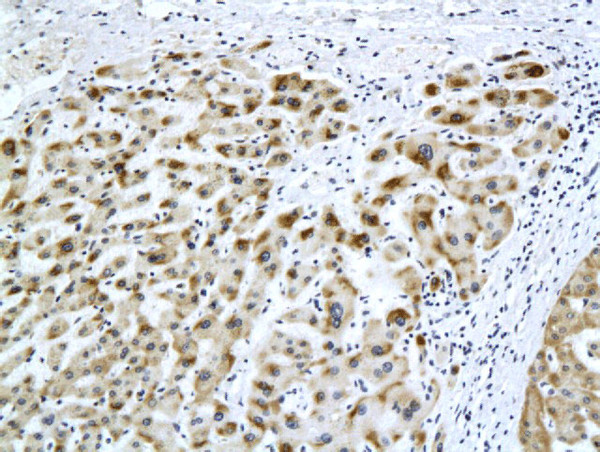

HBsAg Antibody in Immunohistochemistry (Paraffin) (IHC (P))

HBsAg Antibody (BSM-2024M) in IHC (P)

Formalin-fixed and paraffin embedded rat liver labeled with Anti-HBsAg(H2F4) Monoclonal Antibody, Unconjugated (bsm-2024M) at 1:200 followed by conjugation to the secondary antibody and DAB staining. {{ $ctrl.currentElement.advancedVerification.fullName }} 验证信息 View more